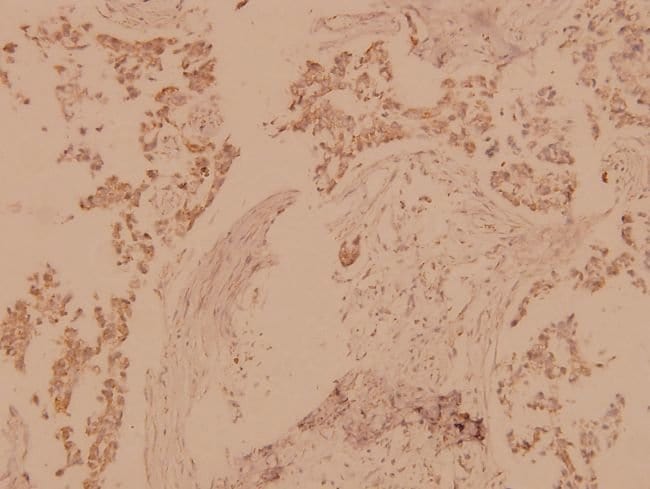

Invitrogen™ MST1/MST2 Polyclonal Antibody

This antibody detects endogenous protein at a molecular weight of 56 kDa. Purity is >95% by SDS-PAGE.

| Immunohistochemistry (Paraffin), Western Blot | |

| Synthetic peptide corresponding to amino acids 150-200 of human MST1. | |